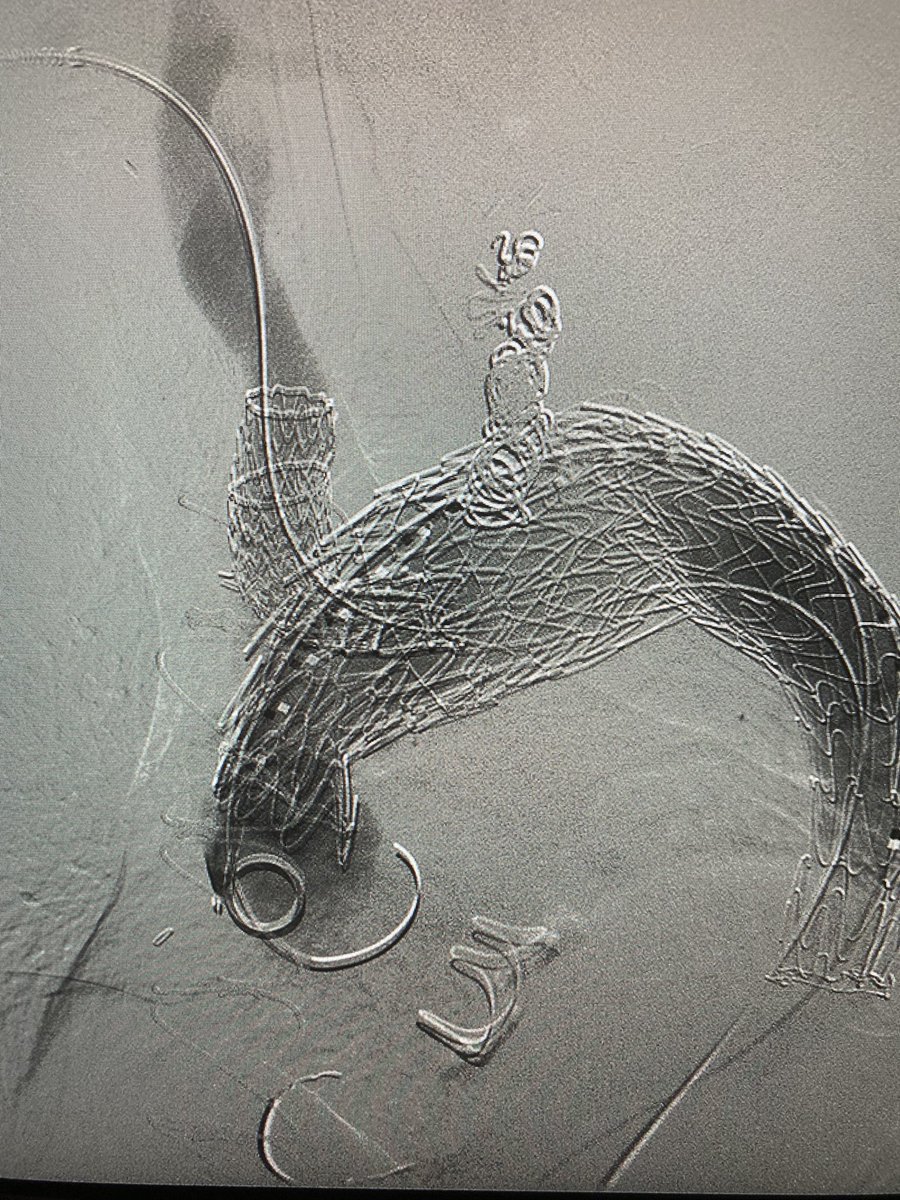

Carotid-carotid carotid-subclavian w/ #endovascular #aneurysm repair for proximal and distal anastomotic aneurysm